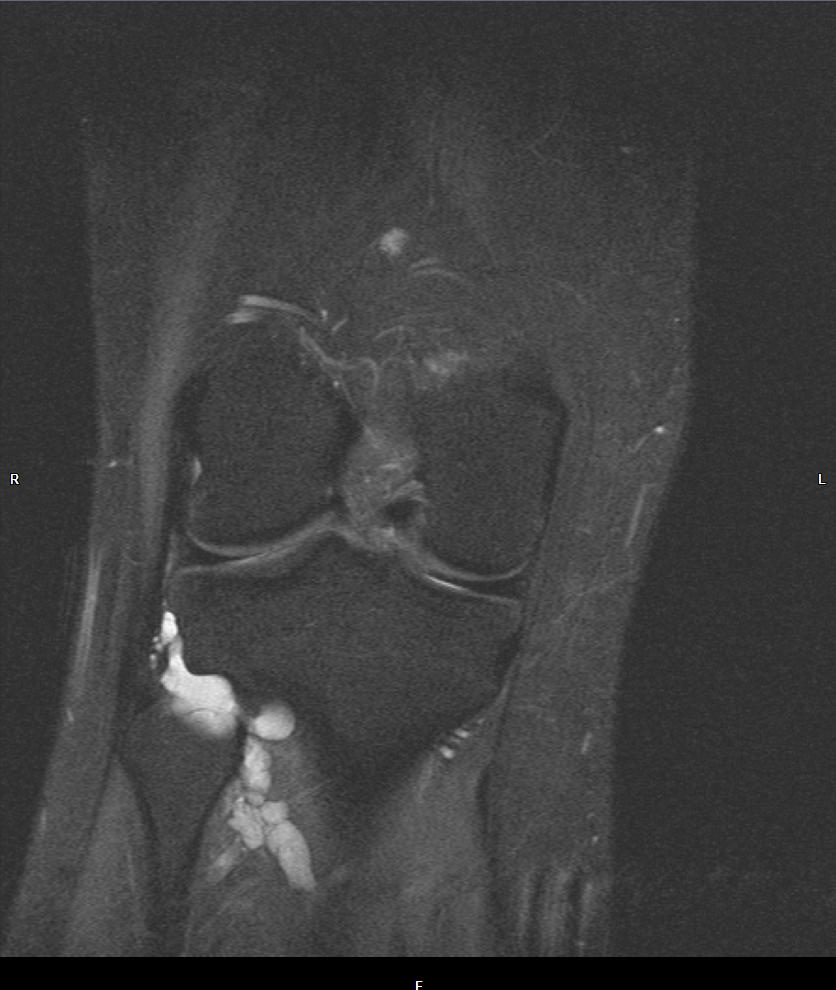

Dann entschied ich mich für ein MRI. Das ist das Bild:

Der Arzt sagte mir, er habe soetwas noch nie gesehen und musste zuerst recherchieren, bevor er mir Antworten geben konnte. Er sagte mir, es sei ein Ganglion. Sie versuchten es zu punktieren, vergeblich. Er sagte, man könnte es operieren, aber es sei ein wichtiger Nerv in der Region. Wenn dieser verletzt würde im Falle einer Komplikation, könnte ich meinen Fuss nicht mehr bewegen. Ich entschied mich dagegen, weil mich die Schmerzen ja nicht wirklich einschränken. Ich dürfe so viel Sport machen, bis ich Schmerzen bekomme.